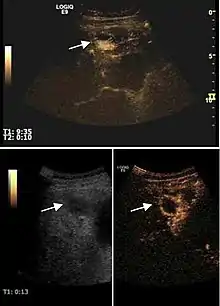

HCC appearance on 2D ultrasound is that of a solid tumor, with imprecise delineation, with heterogeneous structure, uni- or multilocular (encephaloid form). An "infiltrative" type is also described which is difficult to discriminate from liver nodular reconstruction in cirrhosis. Typically HCC invades liver vessels, primarily the portal veins but also the hepatic veins . Doppler examination detects a high speed arterial flow and low impedance index (correlated with described changes in tumor angiogenesis). The spatial distribution of the vessels is irregular, disordered. CEUS examination shows hyperenhancement of the lesion during the arterial phase. During the portal venous phase there is a specific "wash out" of ultrasound contrast agent (UCA) and the tumor appears hypoechoic during the late phase. Poorly differentiated tumors may have a stronger wash out leading to an isoechoic appearance to the liver parenchyma during portal venous phase. This appearance was found in approx. 30% of cases. The described changes have diagnostic value in liver nodules larger than 2 cm.

On CEUS examination, early HCC has an iso- or hypervascular appearance during the arterial phase followed by wash out during portal venous and late phase. There are studies showing that the wash out process is directly correlated with the size and features of neoplastic circulatory bed. Thus, highly differentiated HCC illustrates the phenomenon of late or even very late "wash out" while poorly differentiated HCC has an accelerated wash out at the end of arterial phase. It is therefore mandatory to analyze all these three phases of CEUS examination for a proper characterization of liver nodules. Tumor wash out at the end of the arterial phase allows the HCC diagnosis with a predictability of 89.5%. Some authors consider that early pronounced contrast enhancement of a nodule within 1–2 cm developed on a cirrhotic liver is sufficient for HCC diagnosis. These results prove that for a correct characterization of the lesions it is necessary to extend the examination time to 5 minutes or even longer.

2D ultrasound, Doppler ultrasound and especially CEUS can play an important role in pretherapeutic staging, particularly when sectional imaging investigations (CT, MRI) provide uncertain results or are contraindicated. During the interventional procedure, ultrasound allows guidance of the needle into the tumor. CEUS allows guidance in areas of viable tissue and avoids intratumoral necrotic areas. CEUS also allows assessment of therapeutic effect immediately post-procedure (with the possibility of reintervention in case of partial response) . To accurately assess the effectiveness of treatment it is mandatory to compare the tumor diameter before therapy with the ablation area. The volume of damaged tissue must be higher than the initial tumor volume. CEUS appearance is that of central nonenhanced area showing a peripheral homogeneous hyperenhanced rim due to post-procedure inflammation. 24 hours after the procedure the inflammatory peripheral rim is thinning and the necrotic area appears larger than at the previous examination. Thus, a possible residual tumor may appear more evident. Residual tumor has poorly defined edges, irregular shape, and the tumor diameter is unchanged. Residual tumor tissue is evidenced at the periphery of the tumor as an eccentric area behaving as the original tumor at CEUS examination, with arterial hyperenhancement and portal and late wash-out. Ultrasound examination 24 hours after the procedure, including CEUS, can show apart from the character of the lesion any potential post-intervention complications (e.g. active bleeding).

Local recurrence is defined as recurrence of a hyperenhanced area at tumor periphery in the arterial phase, with portal and late wash-out. Sometimes, especially for HCC treated by alcoholization (PEI) hyperenhanced septa or vessels can be shown inside the lesion.